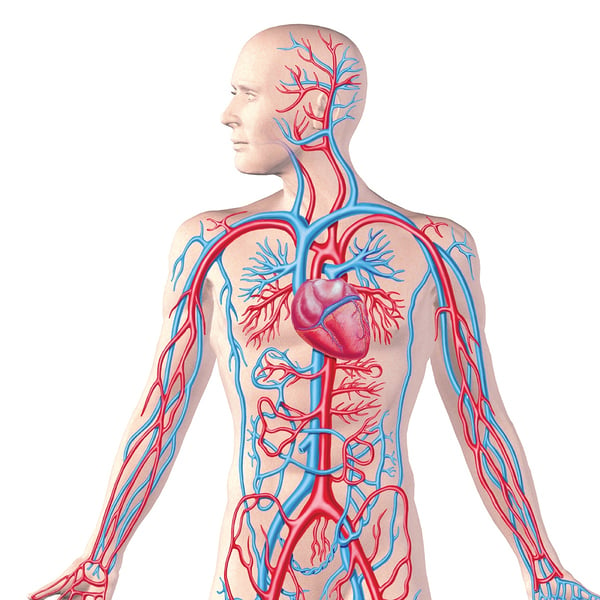

Анатомия человека: кровеносная система и её связь со скелетом